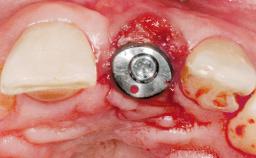

Late Placement of an Implant in a Maxillary Left Central Incisor Site

A 36-year-old female patient was referred for the replacement of the upper left central incisor (tooth 21), which had fractured. Although the tooth had been asymptomatic for many years, the crown began to loosen, at which time she presented to her dentist for an assessment. Teeth 21 and 22 had both been endodontically treated many years previously. She was a healthy individual and a non-smoker.

Type of Implants Two-Piece

Attachment Two-Piece

Abutment Type Customized

Prosthesis Type FDP